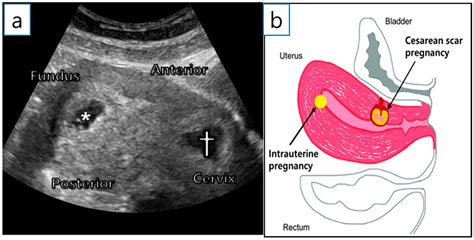

• Previous C section: Women who have had a previous C section may require another C section for subsequent deliveries, depending on the type of uterine incision and other factors.

• Scar tissue: Be aware of the potential for scar tissue formation, which can affect future pregnancies and deliveries.